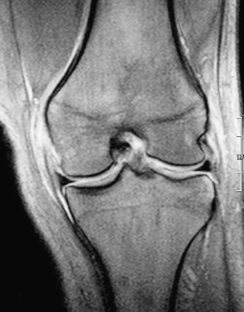

Fig. 4